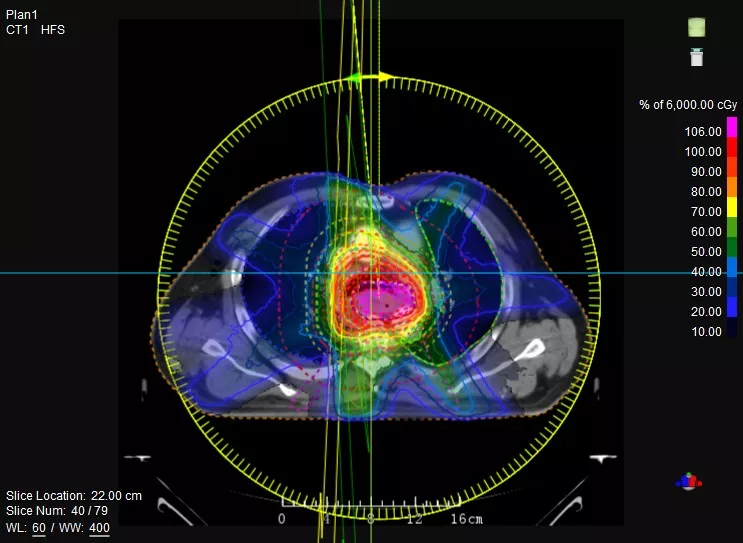

一款設(shè)備即可滿足CT模擬定位、CT影像引導(dǎo)、uARC動(dòng)態(tài)旋轉(zhuǎn)調(diào)強(qiáng)放療等重要臨床應(yīng)用,無(wú)需科室/治療室間切換,一站完成放療全流程。

機(jī)載CT影像可直接用于放療計(jì)劃制作

CT-IGRT配準(zhǔn),除骨性標(biāo)記外,還能以器官、軟組織等作為參考,真正找到配準(zhǔn)目標(biāo)

鼻咽癌患者,進(jìn)行旋轉(zhuǎn)容積調(diào)強(qiáng)治療(uARC)